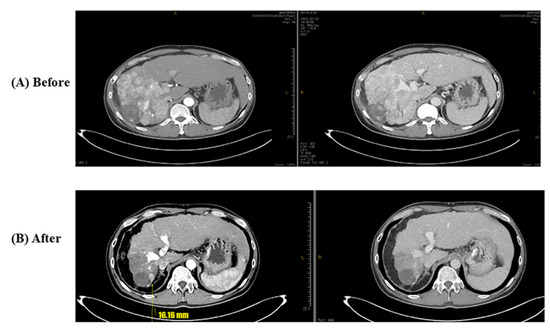

- Case 2